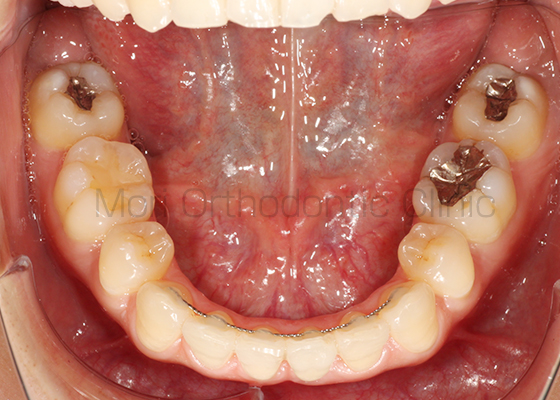

術前

術後

| 主訴 | 歯並び、八重歯 |

|---|---|

| 診断名 | AngleⅡ級叢生 |

| 年齢 | 30歳2か月 |

| 治療装置 | Multi-Bracket(表側矯正)、CARRIERE DISTALIZER |

| 抜歯部位 | 14,24,35,45 |

| 治療期間 | 2年1か月 |

| 治療費 | 825,120円(税込) |

| リスク・副作用 | 矯正治療による歯の移動に伴う痛み、歯根吸収、歯肉退縮、虫歯 |